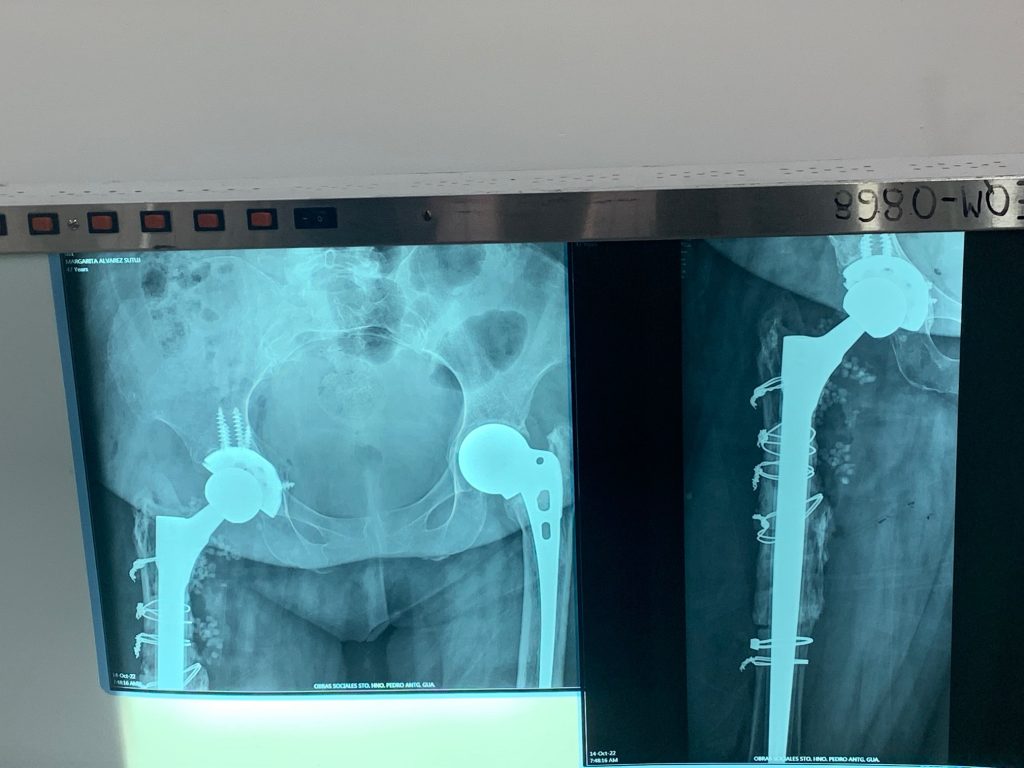

The team was able to sleep in an extra hour today with the morning yoga starting at 6:30 a.m. while a local volcano, de Fuego, was burping out an occasional sign of activity near the surface of the City of Antigua. Surgeons and Physical Therapists made one final trip to the Obras Hospital to complete their final rounds and post-op therapy. Normal patterns of recovery and rehabilitation from total joint replacement and corrective surgery on the lower extremity were observed along with more and more smiles replacing the grimaces shown during immediate post operative recovery. You will see many images of patients walking the halls and climbing stairs with their walker or cane and soon those walking aids will be cast aside as they discover the new capabilities of their repaired skeletons.

One notable knee patient was Juan, a 66 year-old farmer, who underwent primary knee replacement five years ago. One day on the farm, he slipped and fell, knocking his implants loose. After that, he continued his normal farming chores which further loosened and pushed his implants into unintended positions that rendered his knee more and more disabling. At the point when he needed to start using a cane during his farming work, he started to pursue medical help to fix his condition. He was told that he would need to purchase the revision knee implant for him to have his knee fixed. Even though he lived many miles from Antigua, he learned about Team Hope in Motion and that he would be able to receive his implant without any cost from Team HIM. After making the 8-hour journey to Antigua, Dr. Mike Berend performed revision knee surgery removing his existing implants which were malpositioned, creating toxic metal debris that was negatively affecting the muscles and tissue around his knee. A Zimmer Biomet NexGen CCK knee was installed along with Trabecular Metal augments to restore the anatomic position of his knee and allow him to walk normally again. From his hospital bed he spoke about how extremely grateful he was to have a new knee which will enable him to get back to farming and resume his life in a normal fashion.